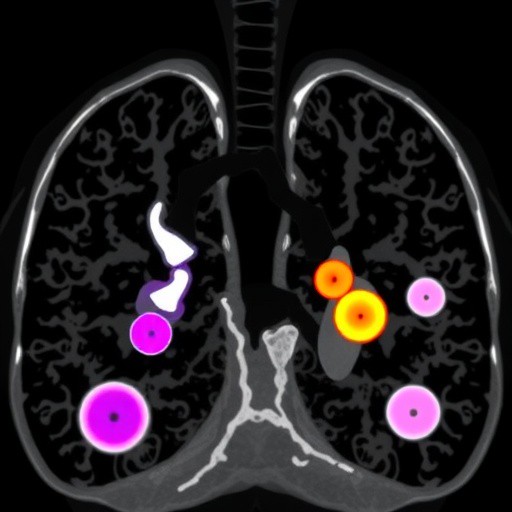

The study retrospectively analyzed 255 pulmonary subsolid nodules from 230 individuals who underwent paired inspiratory and expiratory low-dose CT scans. By comparing the three-dimensional quantitative parameters — including lung volume, nodule diameter (both long and short axes), surface area, volume, and density — between inspiration and expiration phases, the researchers sought to quantify the extent and nature of measurement discrepancies attributable to respiratory variation. The analysis introduced a novel change ratio metric, representing the proportional difference of the parameter measured during expiration relative to inspiration, denoted as (E-I)/I.

Results from this comprehensive evaluation indicated statistically significant differences in all measured parameters of SSNs between inspiratory and expiratory CT acquisitions. Notably, the volume of nodules exhibited the greatest variability, with an average change ratio exceeding 20%. This suggests that volumetric assessments are particularly susceptible to alterations induced by changes in lung inflation, resonating with the understanding that volume measurements inherently magnify dimensional variability due to their cubic relationship to linear dimensions.

Conversely, the long axis diameter of nodules demonstrated the smallest change ratio, approximately 7%, implying that linear measurements along the longest dimension are comparatively more stable across respiratory phases. This disparity in the susceptibility of various quantitative metrics to breathing-related changes presents important clinical implications — particularly that volumetric assessments might overestimate or underestimate nodule growth if the respiratory phase during serial imaging differs.

A further layer of complexity emerged when the influence of nodule density type was analyzed. Part-solid nodules (PSNs) and pure ground-glass nodules (pGGNs) exhibited significant differences in the change ratios of most quantitative parameters, indicating that the degree of solidity within a nodule may modulate its response to inspiration and expiration dynamics. This highlights the heterogeneity among SSNs and suggests that tailored interpretation of CT metrics could be warranted based on nodule composition.

Interestingly, nodule size — subdivided into groups ≤10 mm and >10 mm — did not significantly affect the variability in change ratios, indicating that respiratory phase-induced measurement discrepancies are relatively size-independent within the ranges studied. However, anatomical location within the lung did manifest as a differential factor; nodules in the lower lobes exhibited significantly greater change ratios in density than those in the upper lobes. This likely reflects the greater mechanical movement and volumetric change in the lower lung regions during respiratory cycles.